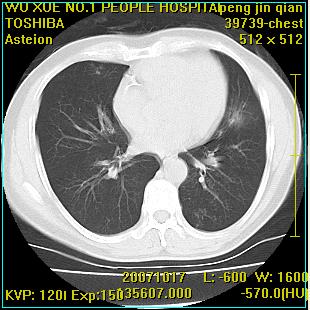

标题: CT10148:男,56岁,咳血。 [打印本页]

标题: CT10148:男,56岁,咳血。

左肺上叶尖段占位性病变,考虑肺癌.癌性空洞,并双肺转移灶及纵隔淋巴结转移

左肺上叶尖后段较大团块影,边缘光滑,内见不规则裂隙样空洞,周围明显见细小结节及渗出,与肺门方向结构紊乱,另:左上叶尖段外侧 舌叶内侧 右上叶尖段及下叶背段均见片状致密影。考虑:继发性肺结核伴空洞形成!

左上肺厚壁空洞影、两肺多发小片样不规则高密度灶。基本上能排除转移瘤。考虑肺结核伴空洞形成。

左上肺后壁空洞,内壁不规则,可见壁结节;左上叶尖段外侧 舌叶内侧 右上叶尖段及下叶背段均见片状致密影。考虑:左肺肺癌并两肺继发性肺结核?

右肺下叶背段/左上肺/左下肺结核伴空洞形成

结核 空洞伴两肺播散

浸润型肺结核伴左上肺空洞形成,两肺播散灶